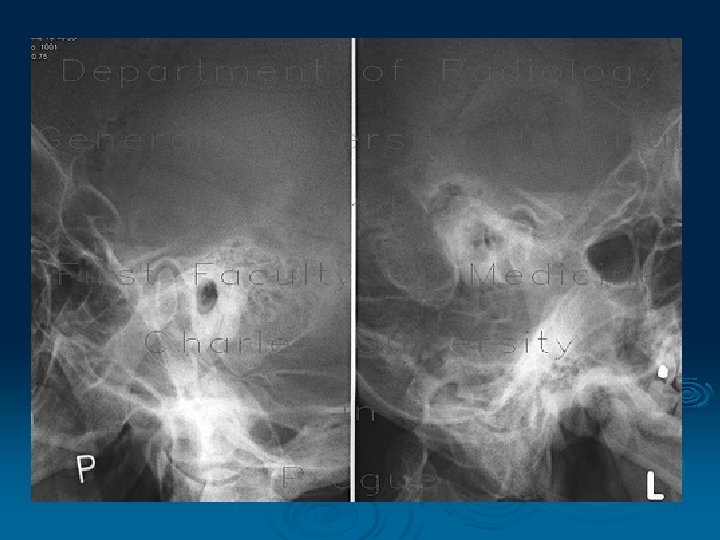

Arthrography: single-contrast arthrography - injection of contrast medium double-contrast arthrography - injection of contrast medium and injection of air